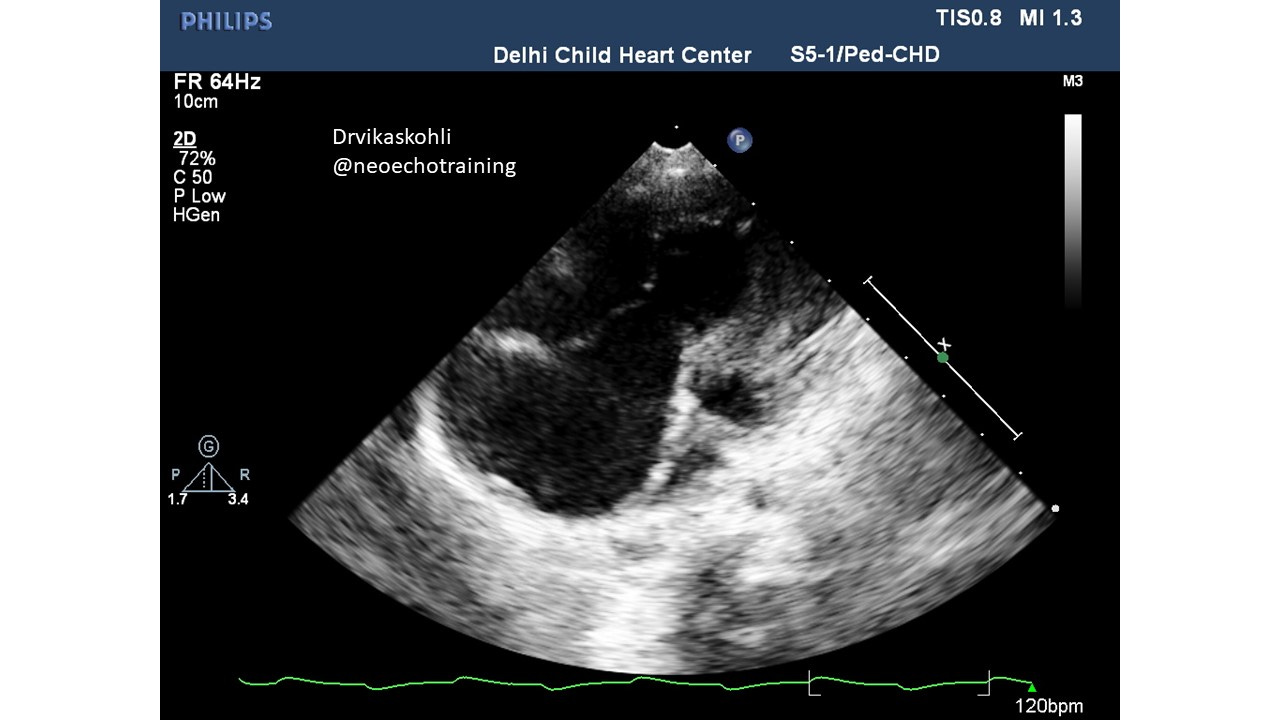

There are other leaflets: anterior and posterior. They may also be abnormal. They could be displaced or could be abnormally large sail-like.

The RV from the true tricuspid attachment to the new septal leaflet attachment is referred to as Atrialized RV.

Which view shows which Leaflet of TCV: